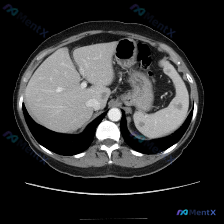

整理了一张很有讨论价值的上腹部平扫CT病例,先把核心信息和我的分析思路放出来: 📋 核心影像表现 图像显示的是上腹部层面,除脾脏外,肝实质、胰腺、胃壁、腹主动脉及腹膜腔在该层面均未见明显异常。唯一的显著异常在脾脏: - 脾脏实质内可见明显的低密度区域 - 边界尚清,但形态欠规则 - 位于脾脏实质内部...

整理了一份脾脏多发低密度灶的CT读片和分析思路,这个病例其实很容易被“边界清”带偏,先把关键信息和我的思考过程放出来: 影像核心发现 单张上腹部CT横断面(软组织窗): - 肝脏、腹主动脉、下腔静脉等周围结构大致正常 - 脾脏实质内见数个类圆形低密度灶,边界相对清晰 - 无明显渗出、炎症或肿大淋巴结...